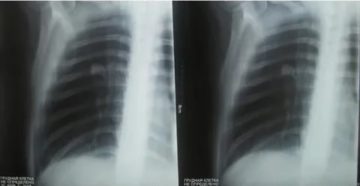

Плевродиафрагмальные спайки в легких: что это такое, в чем опасность? Плевродиафрагмальные спайки – это соединительная…